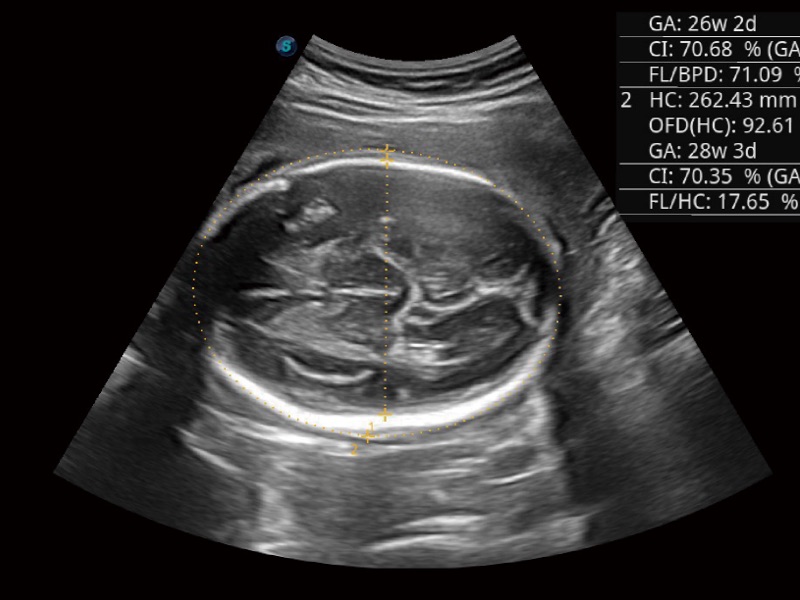

婦產(chǎn)科應(yīng)用

超聲檢查得益于實(shí)時(shí)性、經(jīng)濟(jì)性、便捷性,目前廣泛的應(yīng)用于臨床工作中,超聲檢查設(shè)備已成為幫助臨床醫(yī)生輕松地完成診斷工作的好伙伴。P20 Plus集成了一整套包含了腹部、心血管、小器官、婦產(chǎn)科等全面臨床應(yīng)用功能,輕松應(yīng)對各種臨床問題。